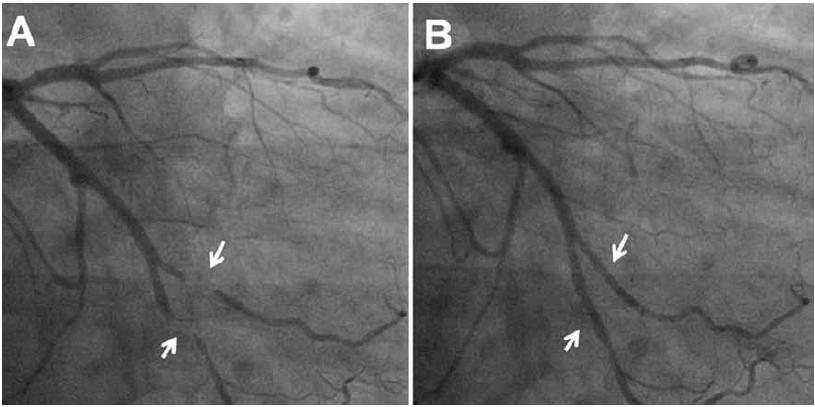

-Angiografía

Es una de las técnicas diagnósticas más usuales en nuestro medio, donde muchas veces se hace el diagnóstico de manera incidental o por sospecha de otras causas de dolor precordial.

El diagnóstico depende del cambio de diámetro entre la sístole y la diástole dentro del segmento coronario con PM. Un “efecto de ordeñe” significativo está presente cuando hay una reducción ≥70% en el diámetro luminal mínimo durante la sístole y una reducción ≥35% persistente en el diámetro luminal mínimo durante la diástole media-tardía (Figura 2).

El estrechamiento sistólico en el PM puede acentuarse mediante la inyección intracoronaria de nitroglicerina, debido a la vasodilatación de segmentos coronarios adyacentes sin puentes.